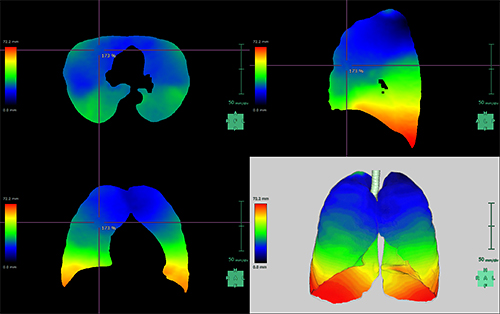

呼吸器領域

肺解析

CT画像から肺野、5葉、気管支を自動抽出。肺結節の解析も可能です。各抽出結果からGoddard分類によるスコアの自動算出、肺葉毎のLAA%の算出、気管支解析やクラスター解析をおこないます。

肺切除解析

CT画像を用いて、肺野、気管支、肺動脈/静脈の抽出を行い、その結果を3D表示します。

また、抽出した血管や気管支の支配領域の抽出、区域分けを行い、術前プランニングを行うことが可能です。

肺換気解析

吸気・呼気の胸部CT画像を元に、各相の低吸収領域を算出。非剛体位置合わせを行い、両者の重複領域も算出できます。さらに呼吸による肺野の移動量を可視化、膨張率も算出可能です。